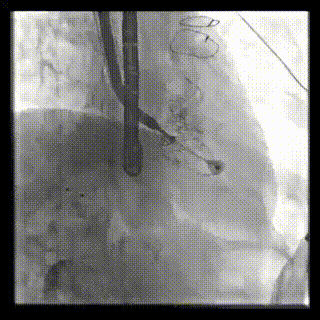

本周三例接受LuX-Valve Plus經血管三尖瓣置換術的患者中,第一例患者為冠狀動脈旁路移植術+Bentall+二尖瓣成形術后;第二例患者為永久起搏器植入術后,存在跨三尖瓣導線;第三例患者合并房顫、房缺及左心耳封堵術后。

三例患者入院后,葛均波院士團隊周達新教授、潘文志教授、張源博士、陳莎莎博士及心超室的潘翠珍教授、李偉教授對患者的情況進行詳細評估和討論,最終決定為三例患者選擇LuX-Valve Plus40mm、50mm和50mm型號的瓣膜進行手術治療。手術后即刻拔除氣管插管,術后患者三尖瓣反流癥狀得到顯著改善,復查心超結果顯示人工三尖瓣瓣膜支架固定穩(wěn)定,瓣葉關閉形態(tài)未見異常,未見明顯反流。

LuX-Valve Plus是LuX-Valve系列產品的第二代,采用的是經血管入路的全新輸送系統(tǒng),其設計開發(fā)過程得到了上海中山醫(yī)院葛均波院士及其團隊的精心指導,研究結果提示瓣膜植入的安全性和有效性俱佳,尤其瓣膜獨特的設計使其具有極佳自適應性,本周三例患者病因及解剖結構各具特點,但均可從LuX-Valve Plus植入術明顯獲益。目前,LuX-Valve Plus已在全國各中心開展救治性臨床研究,相信未來定會為更多的三尖瓣反流患者帶來福音。